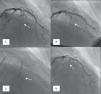

Coronary angiography was then performed to exclude severe coronary disease and to locate the first septal perforator artery. A 0.014-in. guidewire was advanced to engage, in most cases, the first septal branch of the left anterior descending artery (Figure 1A). A slightly oversized, short (∼10mm), over-the-wire angioplasty balloon was then introduced into the septal perforator artery, using standard methods; the lumen of this device provides the route for selective delivery of angiographic contrast, echo contrast, and ultimately alcohol, into the septal artery. After careful fluoroscopic positioning of the balloon (using selective angiography to exclude encroachment onto the LAD), it was inflated and the guidewire removed (Figure 1B).

Angiographic demonstration of alcohol septal ablation technique. Left coronary angiography shows the target septal branch (arrow); an angioplasty guidewire is already inserted inside the septal branch (A). Optimal positioning of the balloon catheter (arrow) in the proximal part of the septal artery without compromise of the left anterior descending artery (B). Injection of angiographic contrast dye through the central lumen of the inflated balloon catheter (arrow) determines the supply area of the septal branch and excludes leakage into the left anterior descending artery or other coronary vessels (C). Final demonstration of the septal artery stump (arrow) after alcohol-induced occlusion (D).

A small amount of angiographic contrast was then injected through the balloon lumen to ensure that there was no spill-back into the LAD or collateral recruitment (Figure 1C). The balloon should not be placed too distally as this may result in a smaller (and solely right-sided) septal infarct, with a consequent reduction in the effect on the outflow gradient. Subsequently, an echocardiographic contrast agent (∼1ml SonoVue, Bracco, Geneva, Switzerland) was injected through the balloon, and the myocardium supplied by the septal artery localized with transthoracic echocardiography (Figure 2). The optimal location within the septum is the point of contact between the anterior mitral valve leaflet and septum in apical four-chamber view. If echocardiographic localization was supportive (no contrast seen outside the thickened basal septum), ablation could proceed. The transvenous pacing wire was re-checked, and intravenous analgesia administered, as the alcohol can cause intense but transient discomfort.

Absolute alcohol (1–3ml) was then administered slowly through the lumen of the balloon, for 3–5 minutes, followed by saline flush under continuous hemodynamic and ECG surveillance. The invasive and echocardiographic gradients were reassessed, a successful procedure being defined as a residual invasive LVOT pressure gradient of less than 50% of baseline value. If the target reduction in pressure gradient was not achieved, alcohol injection was repeated after 5 minutes (1–2ml) within the same perforator branch. If not successful, the procedure was repeated in a second perforator branch. Once success was achieved, the balloon was deflated, and coronary angiography was repeated to confirm the occlusion of the septal branch and the patency of the left anterior descending coronary artery (Figure 1D). Following deflation, the balloon and wire were removed.